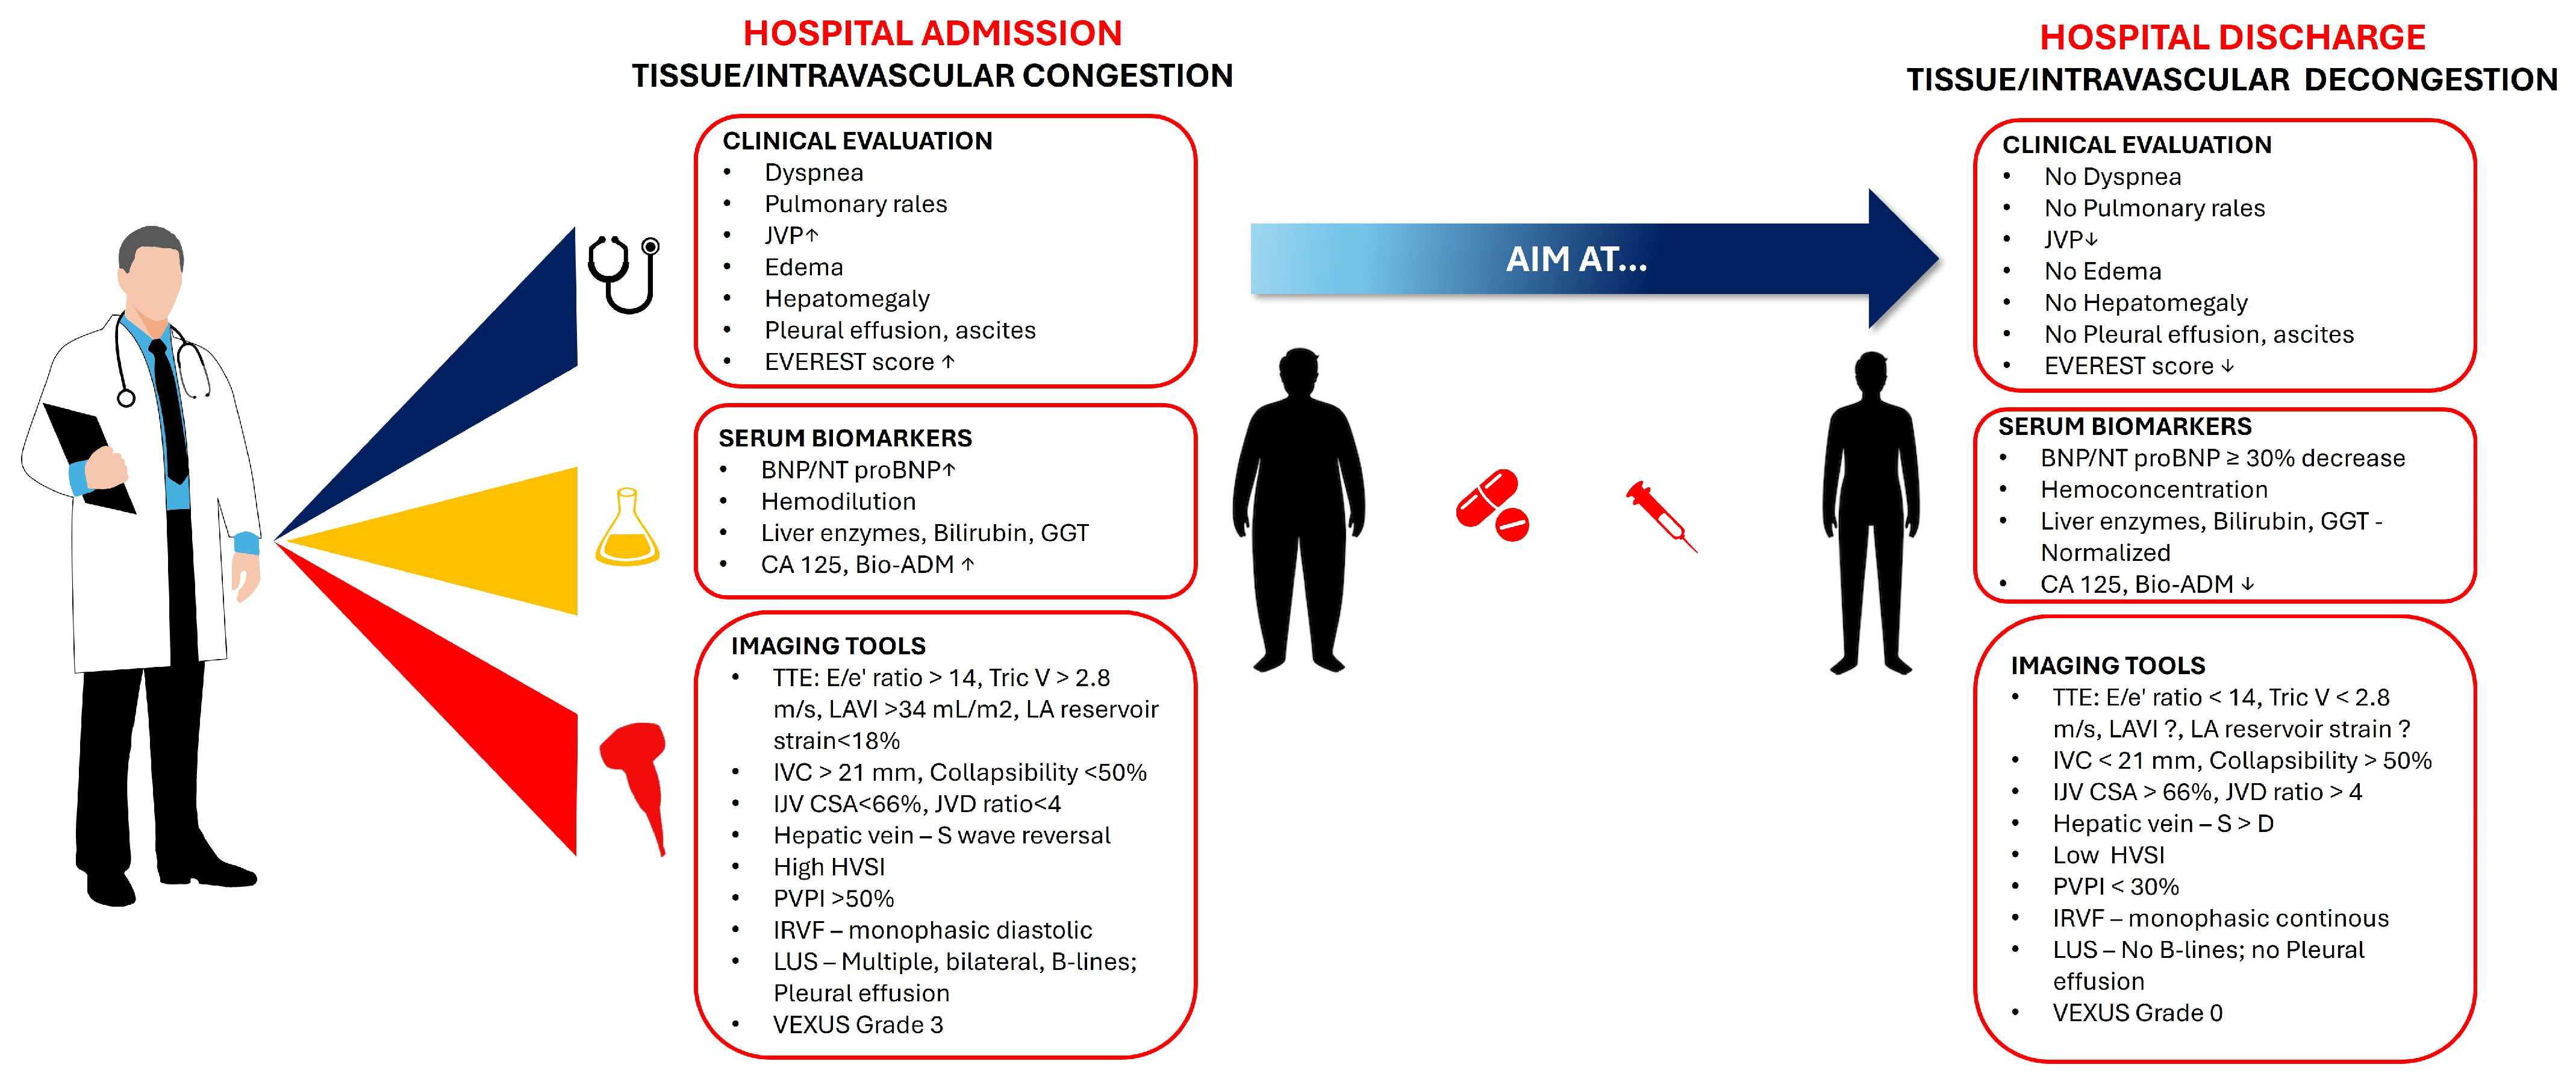

2. Methods of Congestion Assessment and Their Role in Discharge Decision-Making

2.1. Methods of Congestion Assessment

2.1.1. Clinical Evaluation

2.1.2. Laboratory Assessment

2.1.3. Imaging Tools

2.1.4. Integrated Assessment Tools

Integrative, Multi-Parameter Approaches

Proposed Algorithm for Pre-Discharge Assessment

3. Conclusions

| Echocardiography | Estimates LV filling pressures and assesses cardiac function. | Essential for managing HF; provides prognostic information. | Highly sensitive for assessing LVFP; useful in guiding therapy. | Predicts outcomes based on LVFP and cardiac function. |

| Lung Ultrasound | Detects pulmonary congestion through B-Lines. | Highly sensitive and specific for pulmonary congestion. | Useful in clinical decision-making; improves congestion evaluation. | Helps identify patients at risk for poor outcomes. |

| Chest Radiography (CXR) | Assesses pulmonary congestion and pleural effusions. | Useful in emergency settings; limited by interobserver variability. | Detects severe pulmonary congestion; less sensitive than LUS. | Predicts outcomes based on radiographic congestion score. |

| Inferior Vena Cava (IVC) Ultrasound | Evaluates right-sided filling pressures. | Useful in assessing volume status and guiding therapy. | Dilated IVC with reduced collapsibility indicates elevated CVP. | Predicts rehospitalization risk based on IVC diameter and collapsibility. |

| Hepatic Vein Ultrasound | Assesses right heart hemodynamics. | Provides insights into hepatic congestion and right atrial pressure. | Changes in waveform patterns correlate with congestion severity. | Predicts cardiac events based on hepatic venous stasis index. |

| Portal Vein Ultrasound | Evaluates systemic venous congestion. | Useful in assessing portal vein pulsatility and congestion severity. | PVPI ≥ 50% indicates severe systemic congestion. | Predicts outcomes based on changes in PVPI. |

| Renal Vein Ultrasound | Assesses renal hemodynamics and venous congestion. | Useful in identifying patients at risk of complications. | Discontinuous flow patterns indicate severe congestion. | Predicts outcomes based on improvement in renal venous Doppler parameters. |

| Internal Jugular Vein (IJV) Ultrasound | Estimates CVP and guides discharge decisions. | Useful in predicting readmission risk based on IJV compliance. | Normalization of IJV compliance predicts reduced readmission risk. | Predicts 30-day readmission risk based on IJV CSA change. |

| BIVA | Assesses hydration status and body composition. | Useful in detecting subclinical congestion. | Superior to BNP in detecting peripheral congestion; requires specialized equipment. | Helps identify patients at risk for poor outcomes; useful in guiding discharge decisions. |